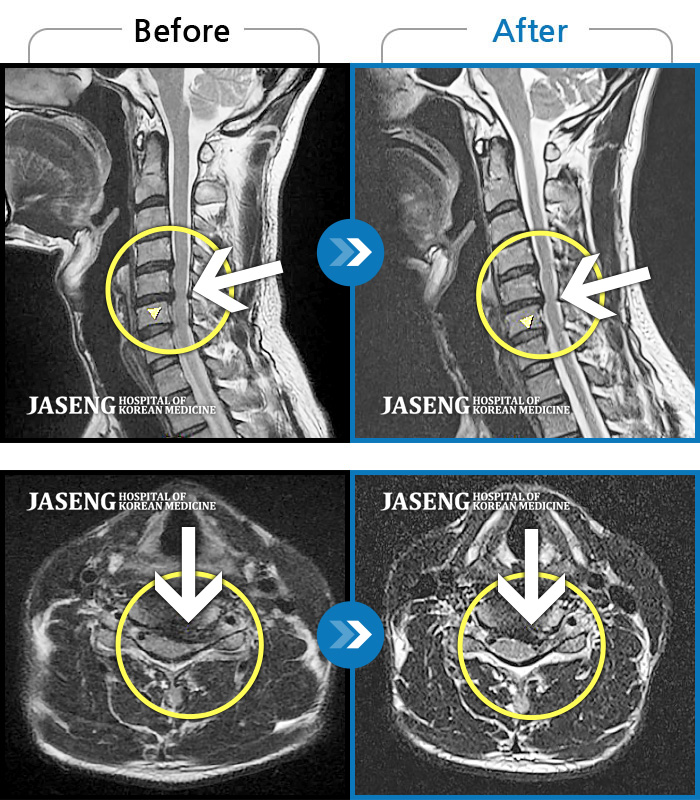

자생 비수술 한방통합치료 후

터진디스크가 흡수된 모습

좌측 승모근부터 견갑골까지 이어지는 통증, 좌측 상완 비증으로 내원하셨습니다.

2024.04.03 ~ 2024.10.24